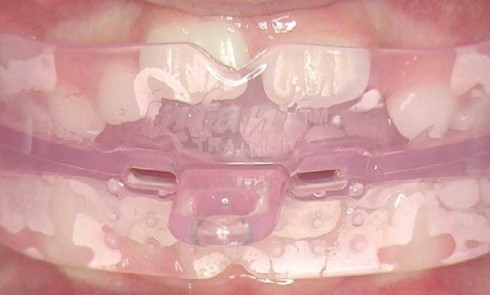

Article réservé à nos abonnés Interception des malocclusions à l’aide des éducateurs fonctionnels

L’interception des malocclusions à l’aide d’éducateurs fonctionnels fait partie de notre arsenal thérapeutique. Elle prend en compte l’ensemble des fonctions...